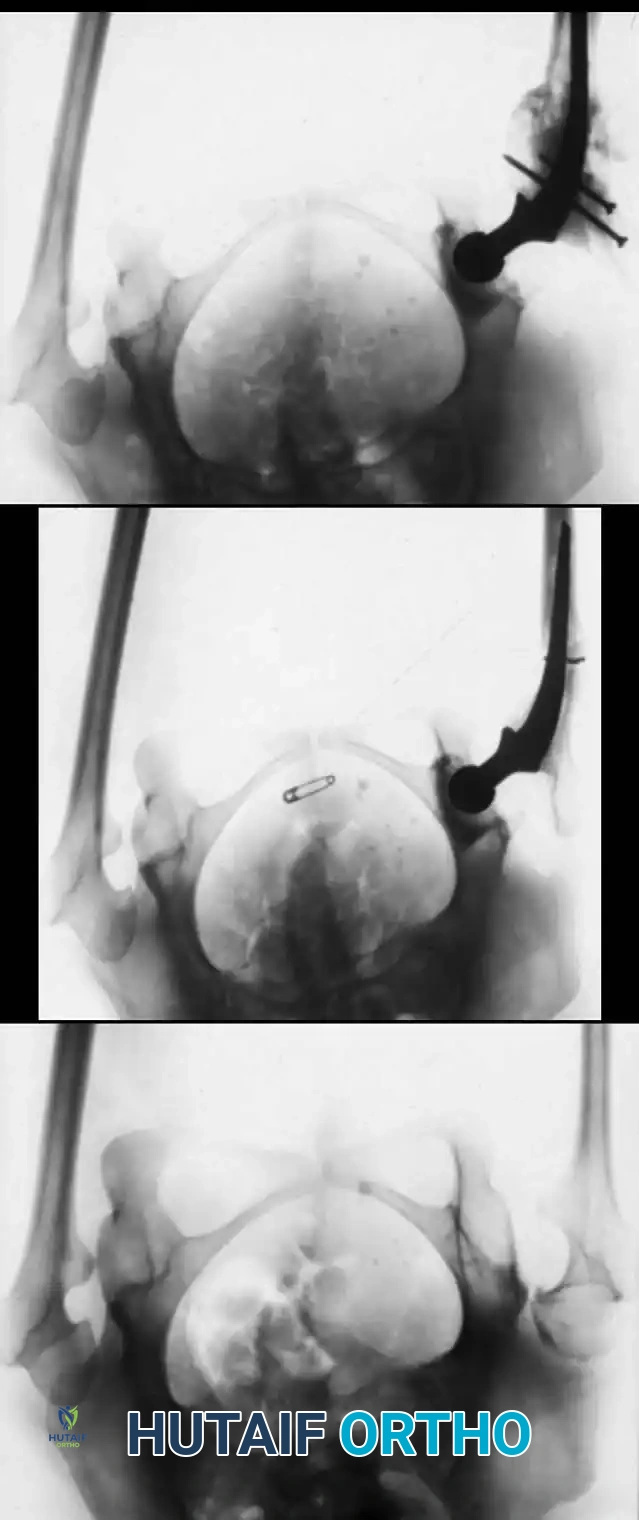

Step 4: Nail Insertion and Epiphyseal Fixation

After the nail has been inserted through the fragments, its distal end must lie in the medullary canal near the distal physis, and its proximal end near the proximal physis.

Tiley and Albright recommended routine central placement of the rod across the physis to add length to the rod and postpone the problem of the rod becoming too short as the child grows. Sofield and Millar reported no disturbances in growth when a smooth medullary nail penetrated the physis centrally. We routinely modify the original technique to extend the medullary nails into the bony epiphysis, resting just short of the subchondral bone plate.

Image

Fluoroscopic confirmation of rod trajectory. The rod must be perfectly centralized within the epiphysis to prevent eccentric physeal tethering or joint penetration.